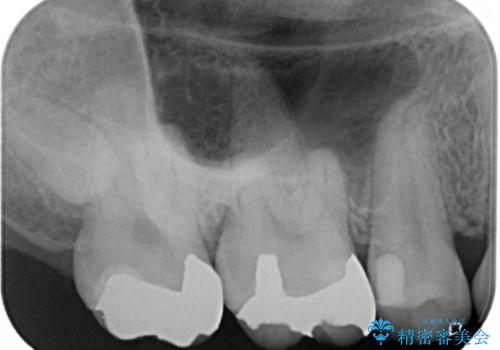

- 右上大臼歯の再治療を希望され来院された患者様です。

切削量と形状を考慮し、インレーでの治療を計画しました。

患者様がゴールドを希望されたのでゴールドインレーを選択しました。

ゴールドは金属の中でも硬すぎず破折すこともほとんどないため歯科の治療に適した材料と言われています。